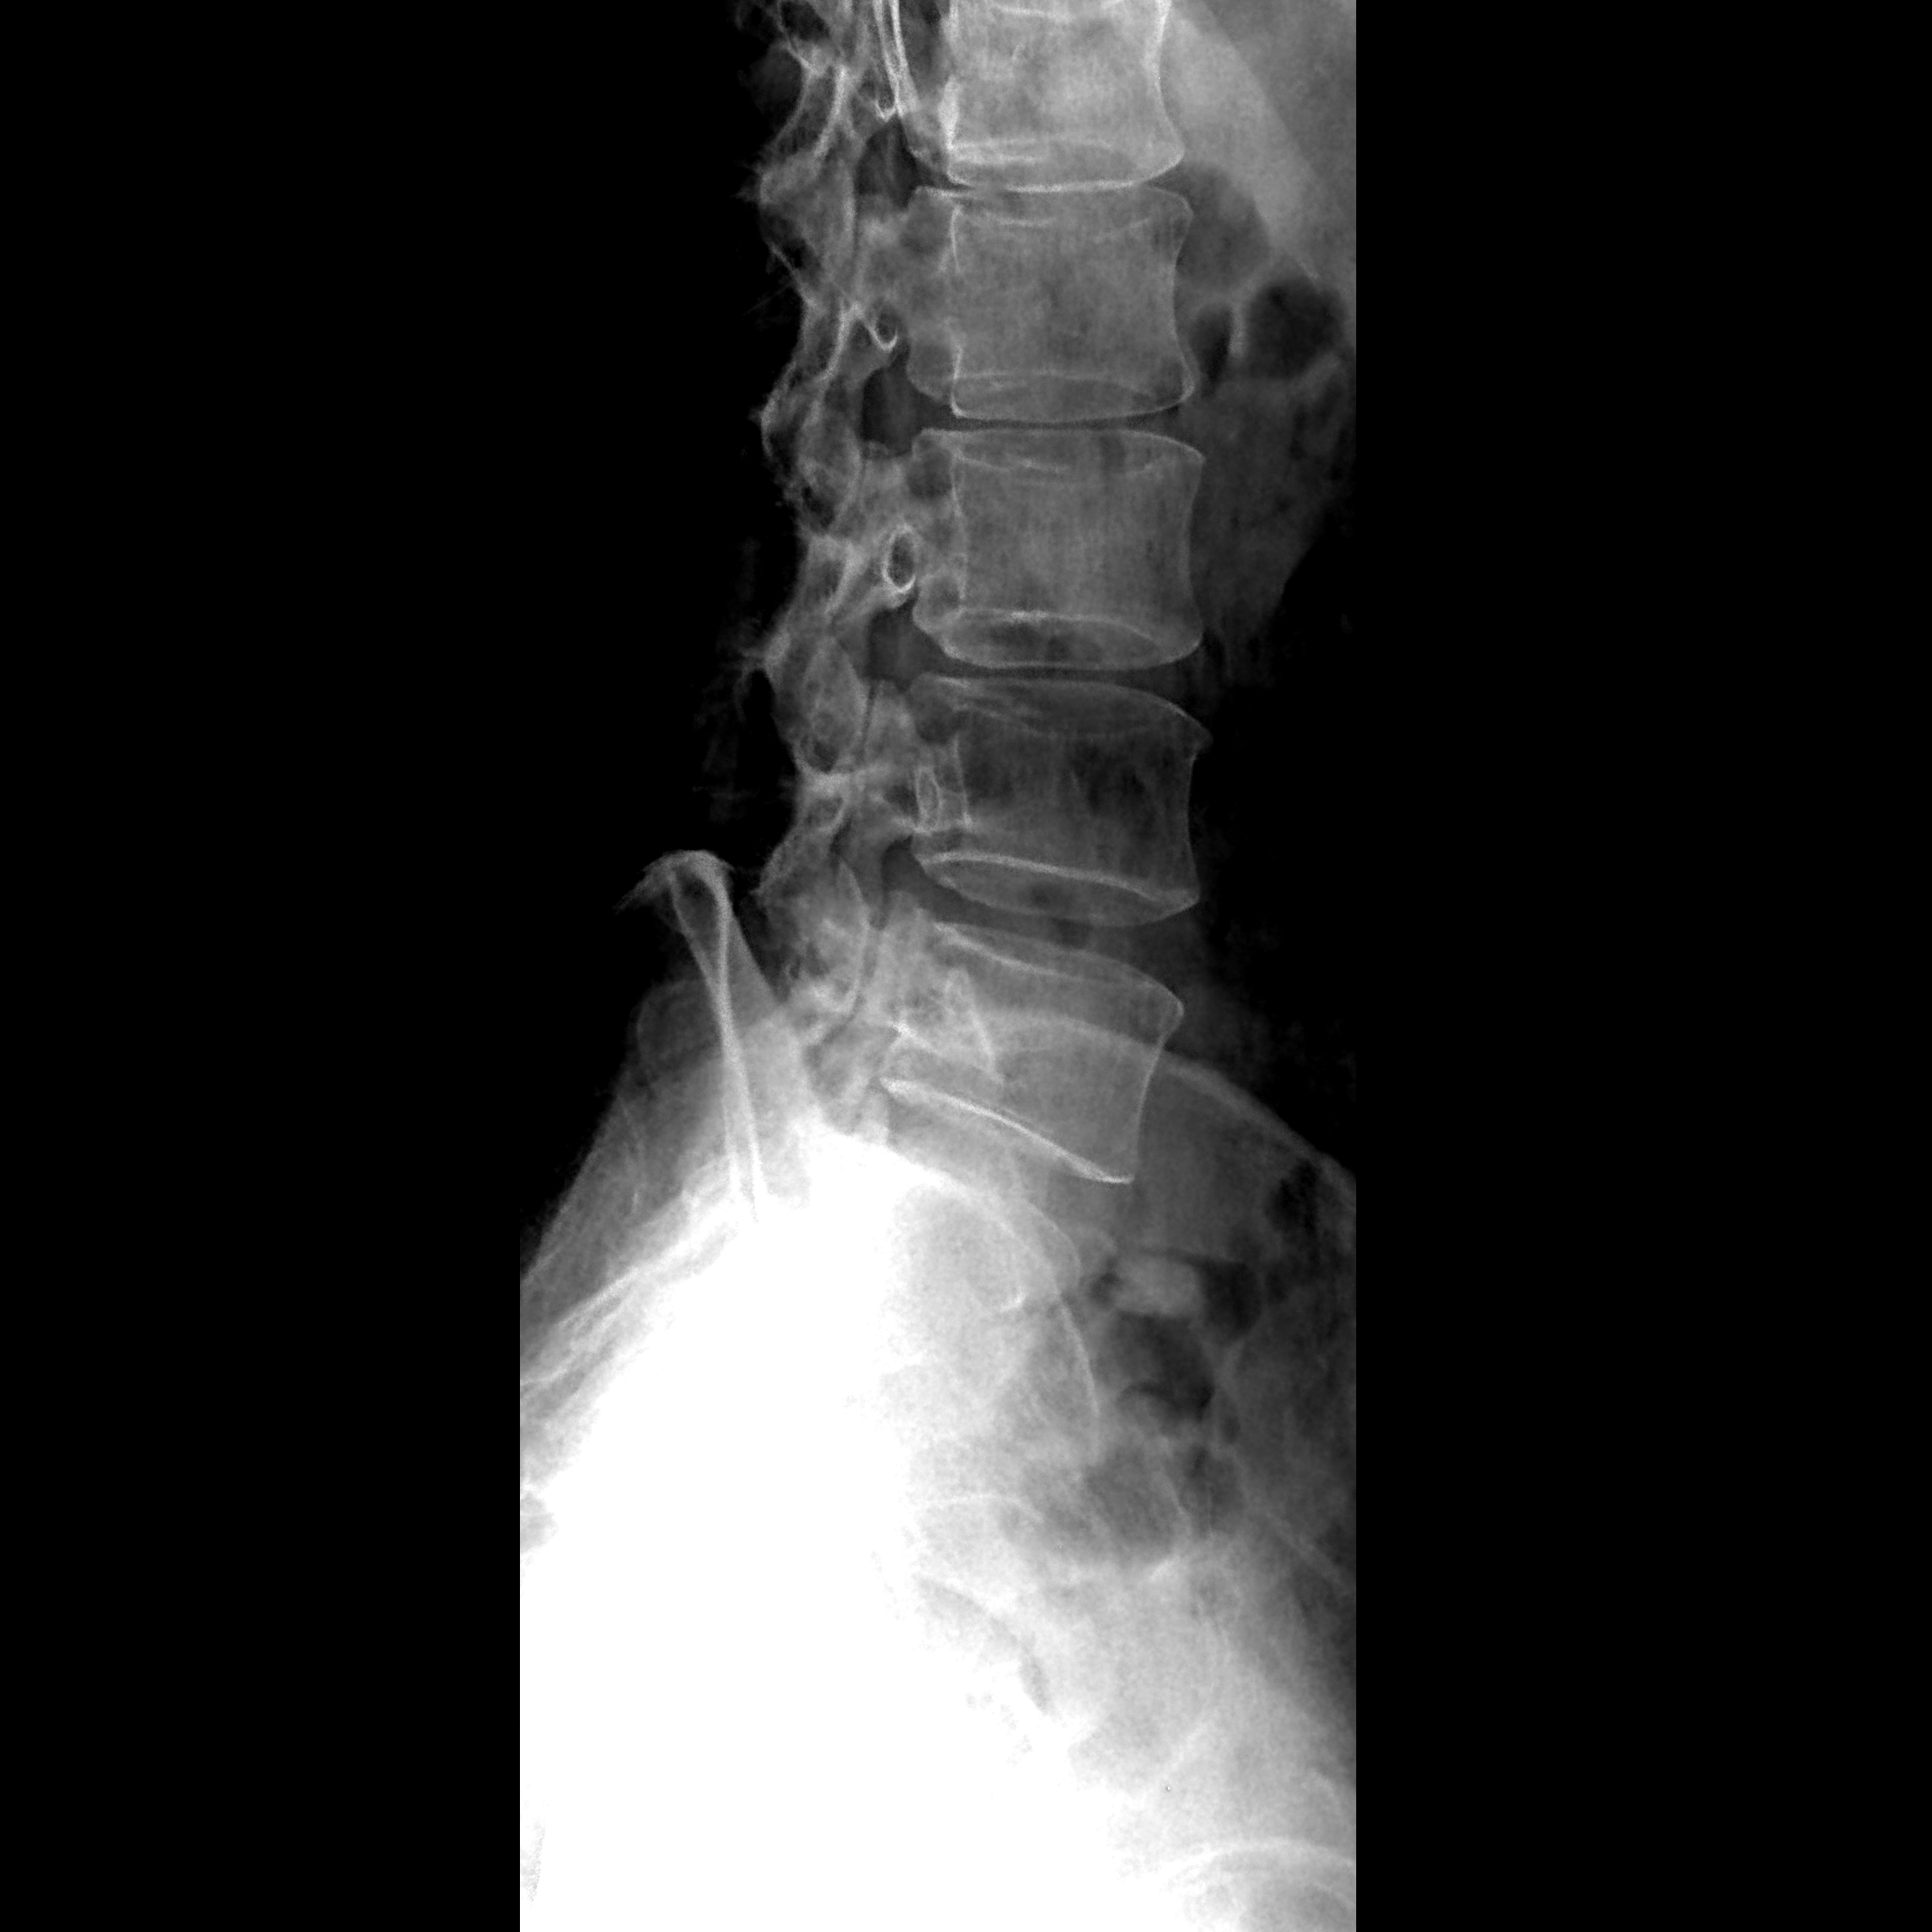

X射线影像可以显示出人体内部的骨骼结构和组织密度,帮助医生诊断骨折、肿瘤、感染和其他疾病。X光机在医学诊断中起着至关重要的作用,它能够帮助医生及时发现和治疗疾病,保障患者的健康。

X射线是通过X光机产生的一种高能电磁辐射,它能够穿透物体并在X射线影像上显示出物体的内部结构。X光机在医学诊断中发挥着重要作用,帮助医生诊断和治疗各种疾病,保障患者的健康。